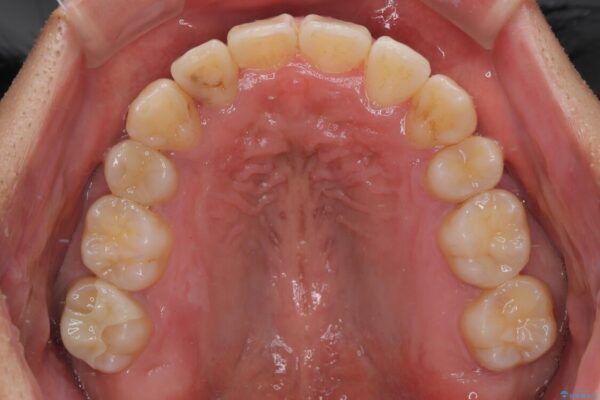

上下の前歯部に強い叢生(ガタガタの歯並び)があり、そのまま歯を並べると出っ歯になってしまう可能性がありました。

そこで、上下左右の第一小臼歯を抜歯し、歯が並ぶためのスペースを確保し叢生を解消する治療計画を立てました。

治療前

• 八重歯と前歯のガタガタを抜歯矯正で治療|クリアブラケット使用例 治療前画像